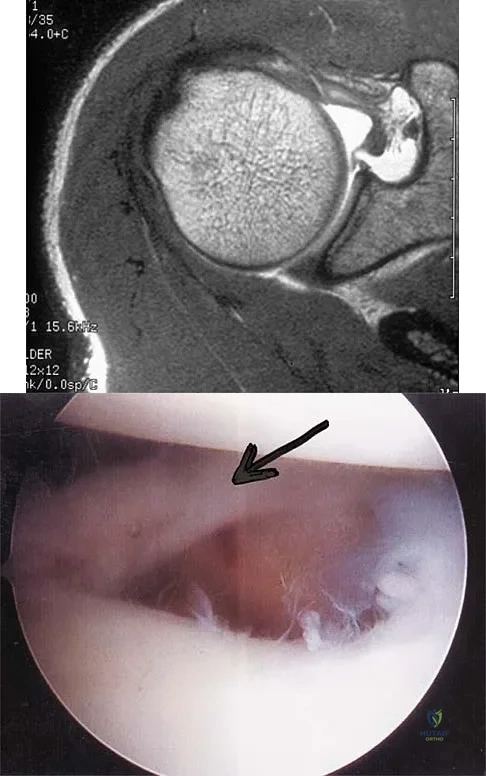

A patient has right shoulder pain. Figure 1a shows a gadolinium-enhanced transverse MRI scan at the level of the coracoid. Figure 1b shows an arthroscopic view of the anterior structures from a posterior portal. These images reveal which of the following findings?

Explanation